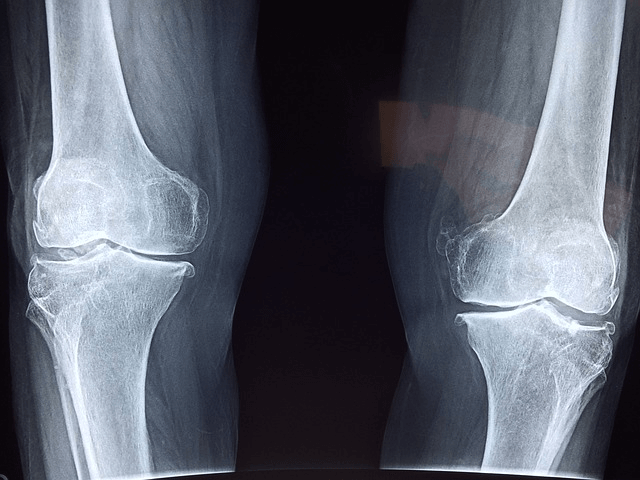

줄넘기와 마찬가지로 10분이면 충분히 끝나는 간단한 운동이지만 무릎과 다리를 많이 주로 이용하니 성장판을 자극해 주고 하체를 튼튼하게 해주는 아주 좋은 유산소 운동입니다. 커가면서 공부하는 힘은 하체에서 나온다고도 하듯 특히 남자아이들은 축구와 같은 운동을 위해서라도 튼튼한 하체가 중요하다고 합니다.